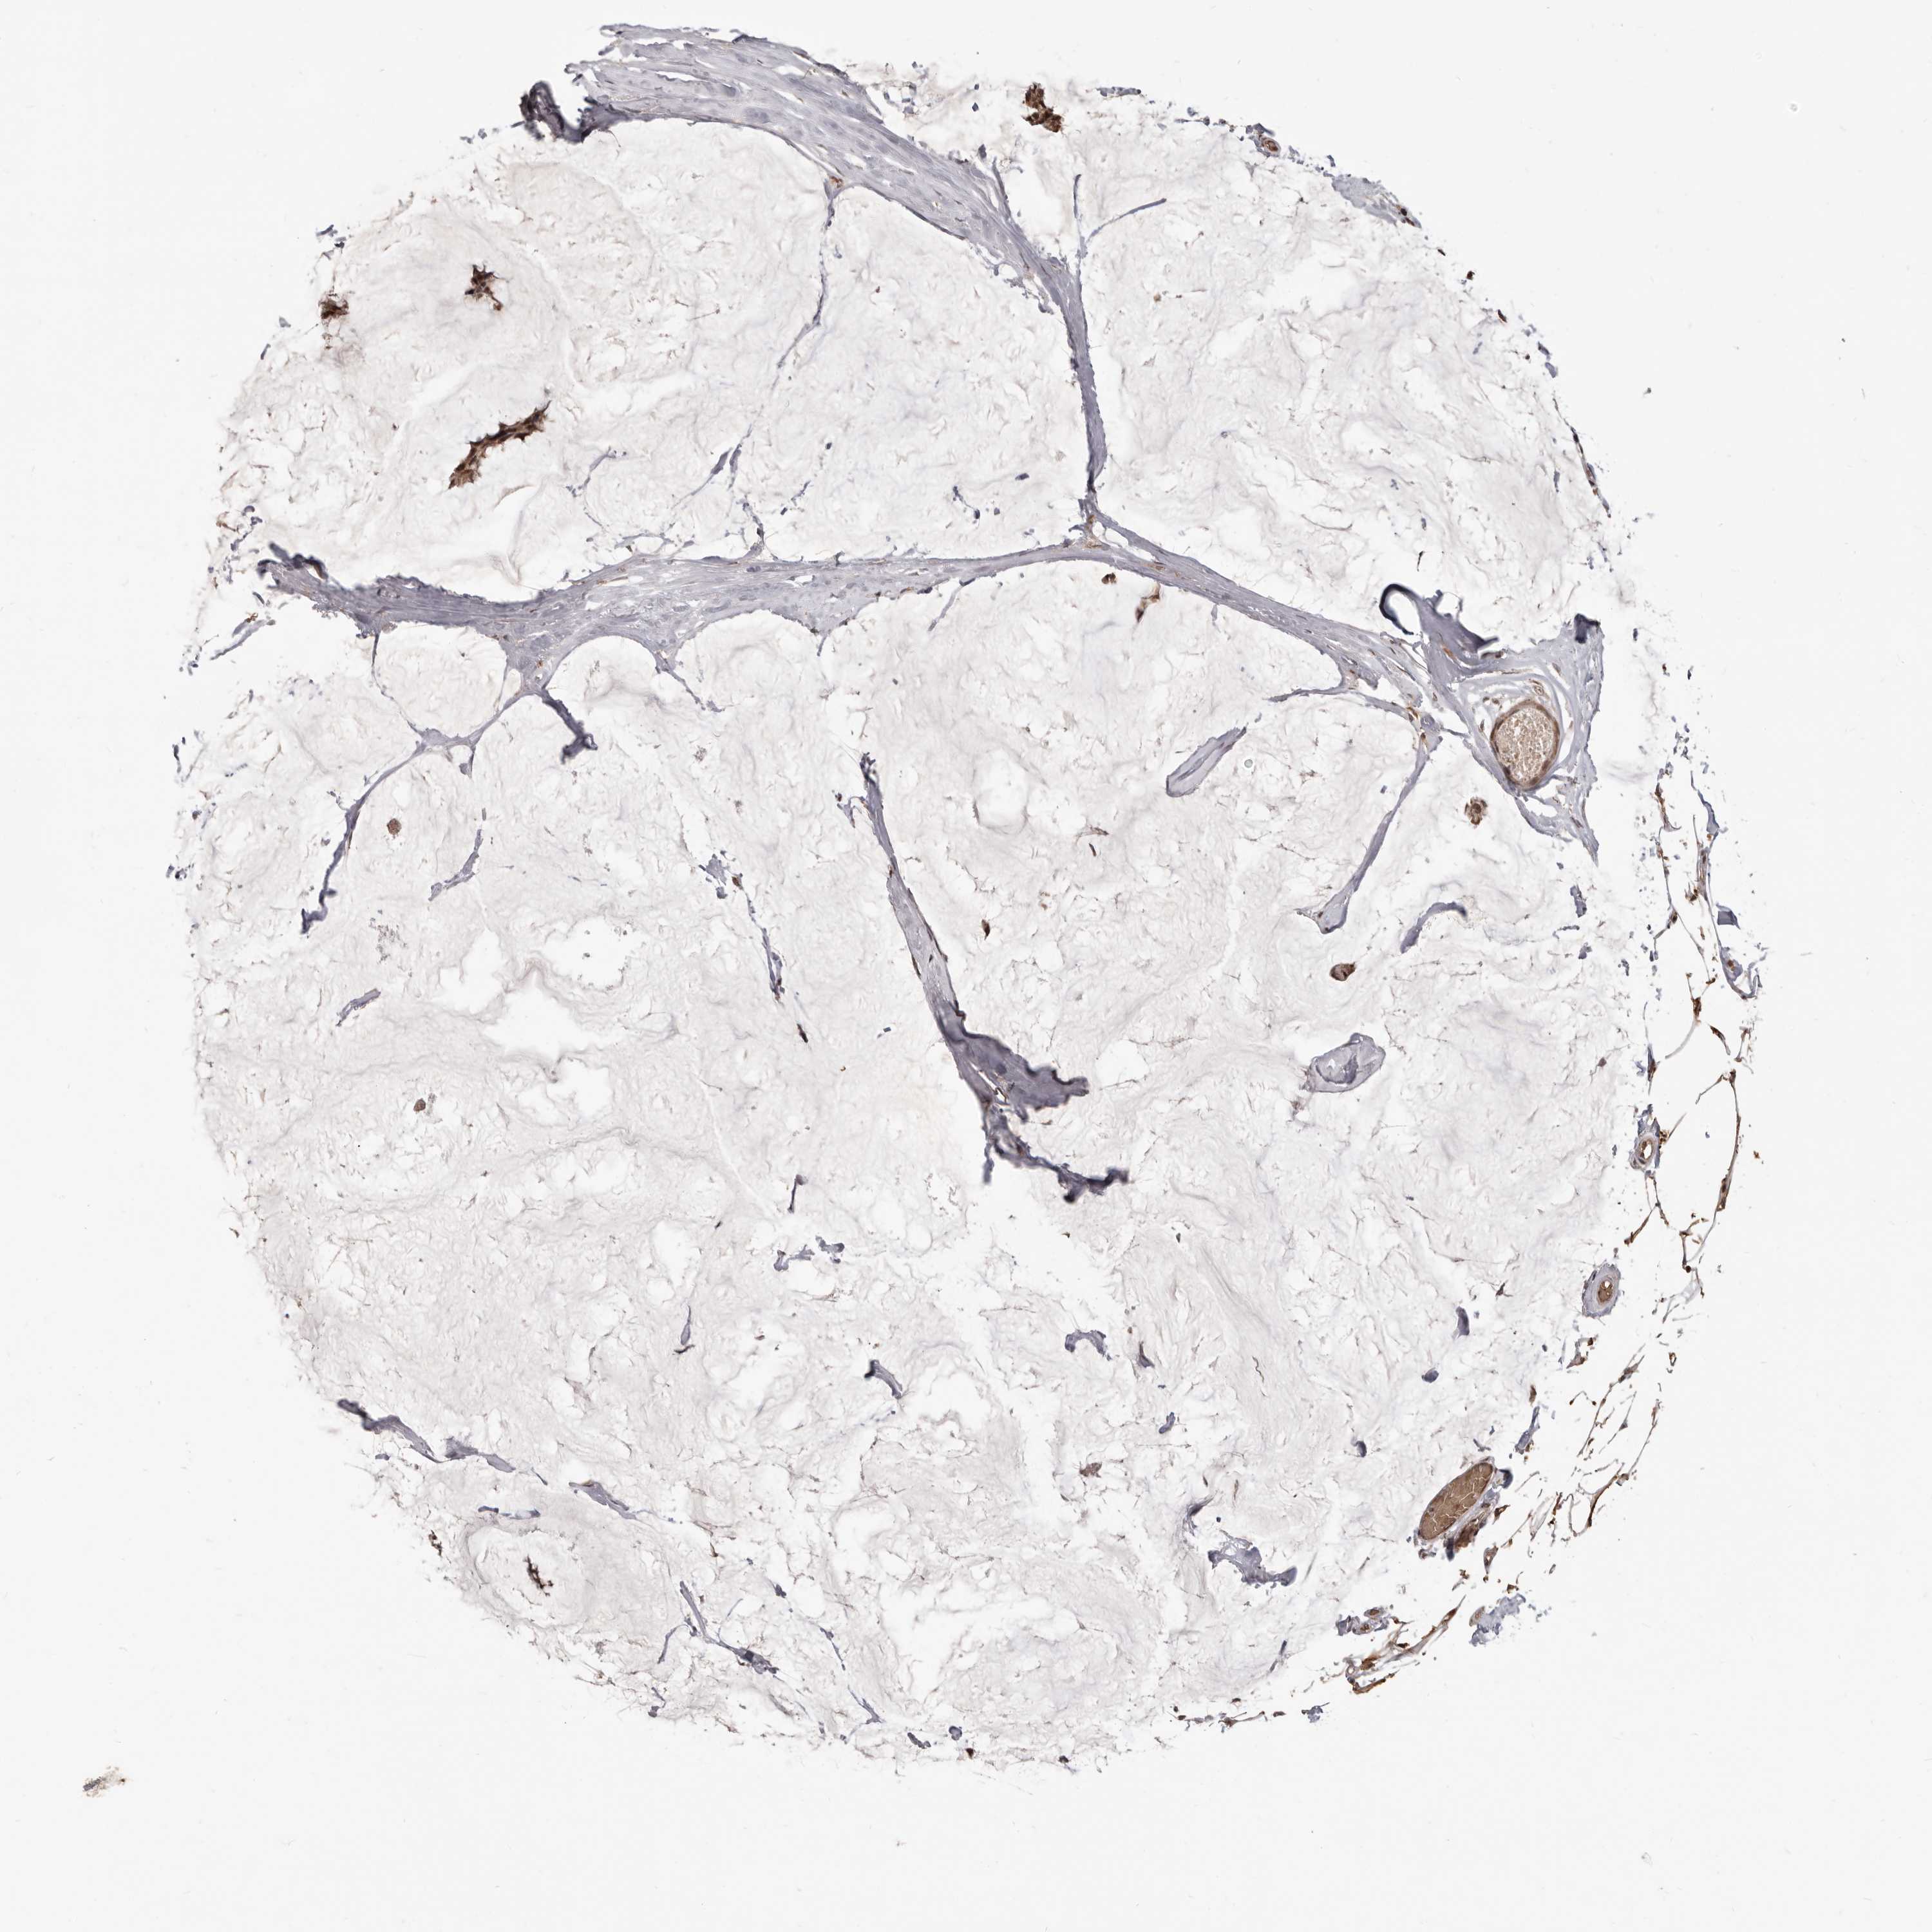

BRCA TCGA BRCA VALIDATION PROTEIN EXPRESSION

ANTIBODIES

AND

VALIDATION